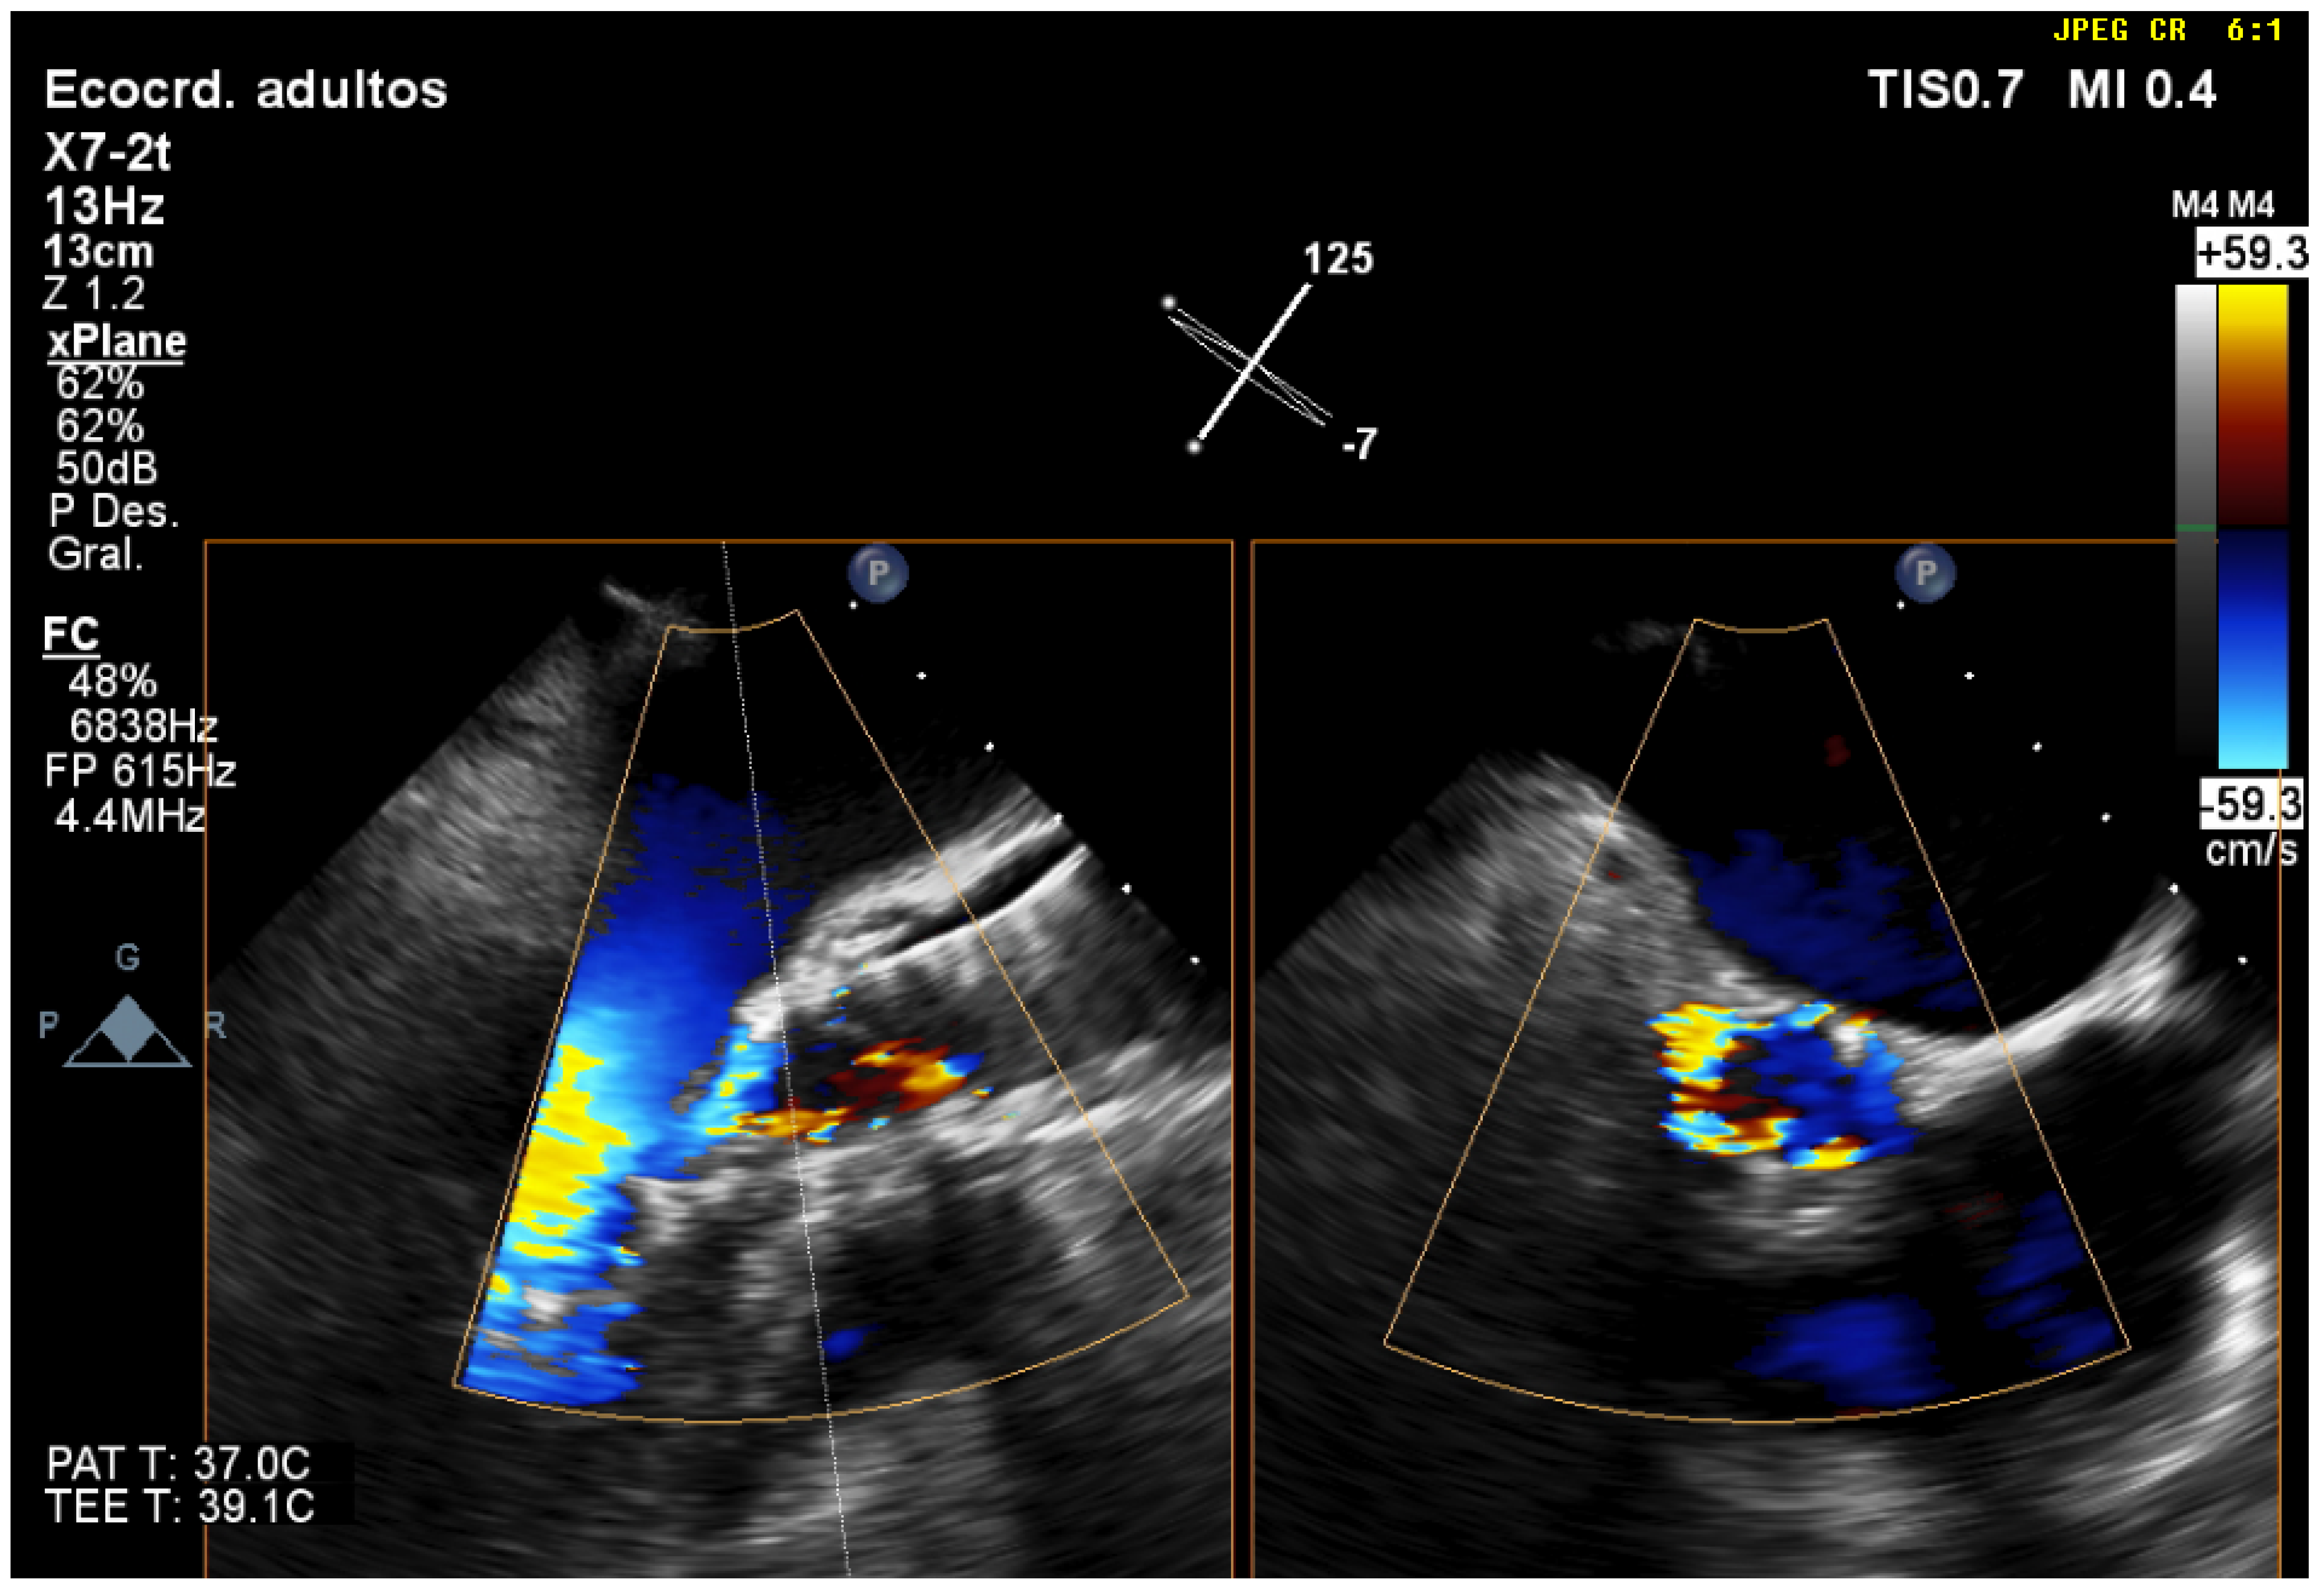

| 2 | TEE monitoring during TAVR implantation allows us to properly position the valve in the aortic annulus, avoiding positioning errors and possible migrations of the prosthesis. |

| 3 | Three-dimensional TEE is the best technique to detect and quantify perivalvular regurgitation after TAVR implantation, a fundamental aspect in deciding whether immediate valve postdilation is needed or not. |